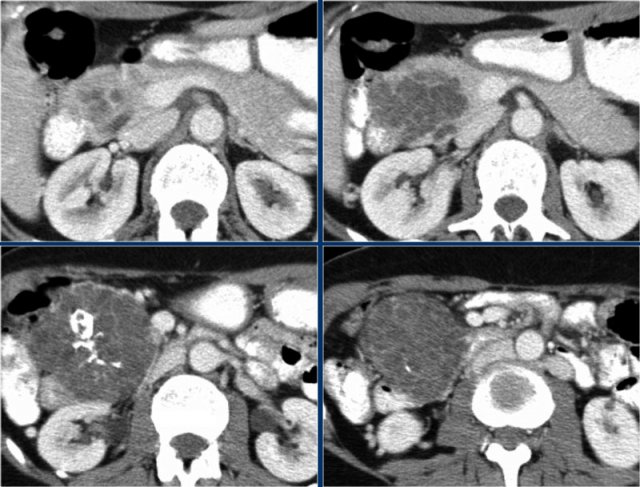

Another example of a serous cystic neoplasm (Fig).

The contrast-enhanced image on the right shows a hypodense lesion with central calcification in the body of the pancreas and subtle enhancement of septations

Notice that on CT it is very difficult to appreciate the cystic nature of these lesions and you might think that you are dealing with a pancreatic adenocarcinoma.

MRI will easily demonstrate the cystic nature of these lesions (fig).

The T2WI with fatsat nicely demonstrates a lobulated hyperintense lesion with central scar, which is characteristic of a SCN.